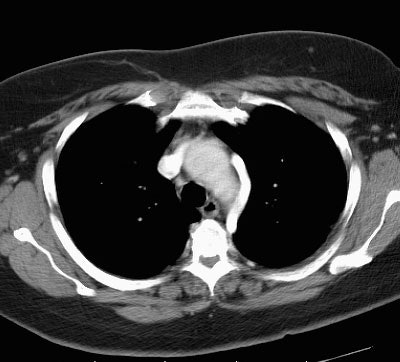

Aortic Nipple:

On chest X-ray the aortic nipple appears as a small nubbin along the superolateral aspect of the aorta (yellow arrow).